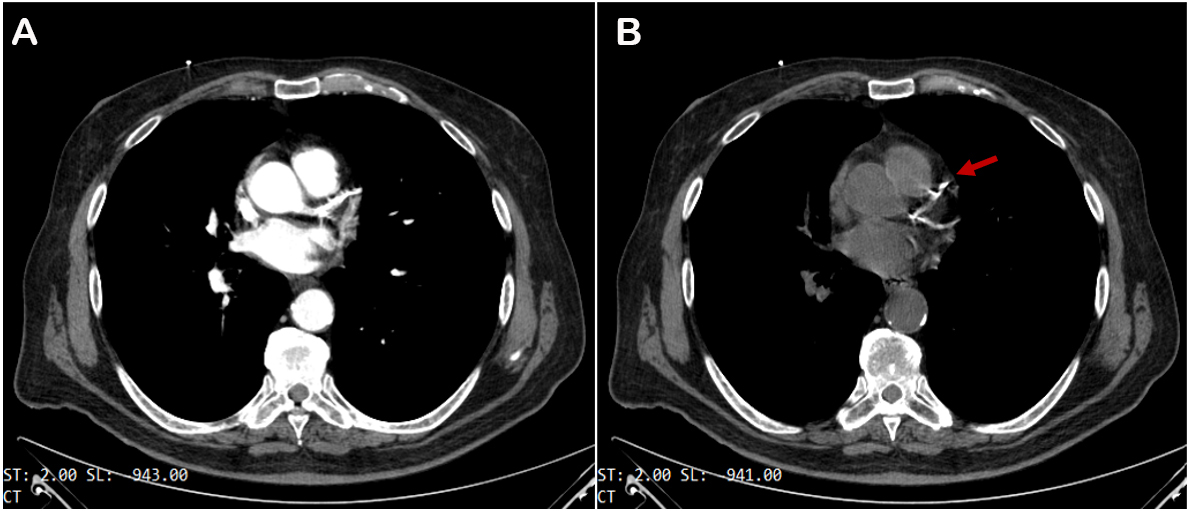

Coronary computed tomography angiography (CCTA) is the principal noninvasive imaging technique used to spot calcium. It has high diagnostic accuracy for identifying coronary artery disease (CAD), pivotal in managing patients with low-to-intermediate pre-test likelihood of CAD[2] and in patients with stable chest pain, as demonstrated by the SCOT-HEART study[3]. Calcium is identified as a zone of hyper attenuation, determined by at least one mm2 with > 130 Hounsfield units or ≥ three adjacent pixels using the Agatston method[4] [Figure 1]. Non-contrast CT scan offers the possibility of obtaining coronary artery calcium scoring (CACS), which has a robust prognostic value in the mid to long term in asymptomatic individuals[5]. CCTA can accurately quantify coronary stenosis severity (volume and extension) and characterize coronary atherosclerosis by detecting spotty calcification; the latter, together with low CT attenuation, remarkable positive remodeling, and the “napkin-ring sign”, represents one of the four signs of vulnerable plaques[6]. Regarding spotty calcification, several studies have demonstrated the key role of 18F-NaF Positron Emission Tomography (PET) in identifying the microcalcification[7], as a marker of active mineral deposition in the atherosclerotic plaque[8]. Therefore, this tracer can be useful in detecting vulnerable plaque[9] and patients with elevated CAD risk[8,10].

Figure 1. Coronary computed coronary angiography with (A) and without (B) contrast media injection. Calcium deposits show up as bright white spots in coronary vessels (red arrow).

However, extensive coronary calcification may compromise image quality due to blooming and beam-hardening or “streak” artifacts, resulting in under- and overestimation of lumen stenosis[2]; these historical limitations are being potentially challenged with emerging technologies[11], from subtraction technique[12] to artificial intelligence software. A recent study demonstrated that the Enhanced Super-Resolution Generative Adversarial Network (ESRGAN) could suppress the blooming artifact improving the specificity and Positive Predictive Value of CCTA[13]; another study has shown a significant impact of Virtual Monoenergetic Imaging and Quantum Iterative Reconstructions in the accuracy of CACS, using a virtual noniodine reconstruction algorithm on a first-generation, clinical, photon counting detector CT system[14].